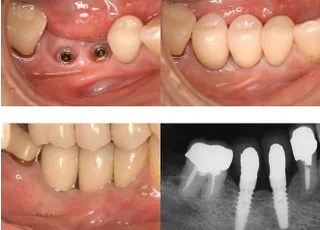

インプラント

快適な食生活と噛める喜びを

インプラントとは歯をむし歯や歯周病、外傷などで失った場合に、あごの骨に人工の歯根を入れる治療です。過去には部分入れ歯しか方法がなかった口の中に、インプラントで歯を入れられるようになりました。

入れ歯と比べて取り外しする必要もなく、歯ごたえのある物もしっかり噛めるようになり、見た目も自分の歯とほとんど変わりはありません。しかし、インプラントは誰にとっても合う治療とは限らず、口の中全体や将来的なことを含めて選択する必要があります。

極端に言えば患者さまが希望しても、条件に適さない場合は別の方法をお勧めする場合もあります。当院では、説明に十分な時間をかけ、患者さまに可能な限りご理解していただいた上で、ご納得いただける方法を提案します。